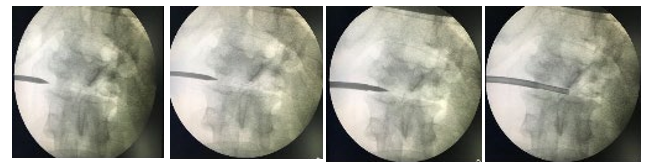

Transpedicular approach [Figure 1]- The patient is placed in the prone position under local anaesthesia and the needle is intro- duced along the course of the pedicle to penetrate the vertebra at the groove between the transverse process and the lateral aspect of the superior articular facet. In this area the cortex is thin and the biopsy needle is inserted perpendicular thereby decreasing the incidence of slippage. More than 50% of the cancellous bone the vertebral body is accessible through this approach. The potential risk of this procedure is violation of the inferior and medial wall of the pedicle, which may lead to hematoma formation, or infection into the spinal canal, which can give rise to spinal cord compro- mise. Consideration of dimension of the trephine and the pedicle is always mandatory. The needle should always be towards the supe- rior and lateral wall of the pedicle. The needle is placed in caudal to cranial angulation than a traditional vertebroplasty approach in an attempt to access intervertebral disk and endplate

Figure 1: Transpedicle Biopsy